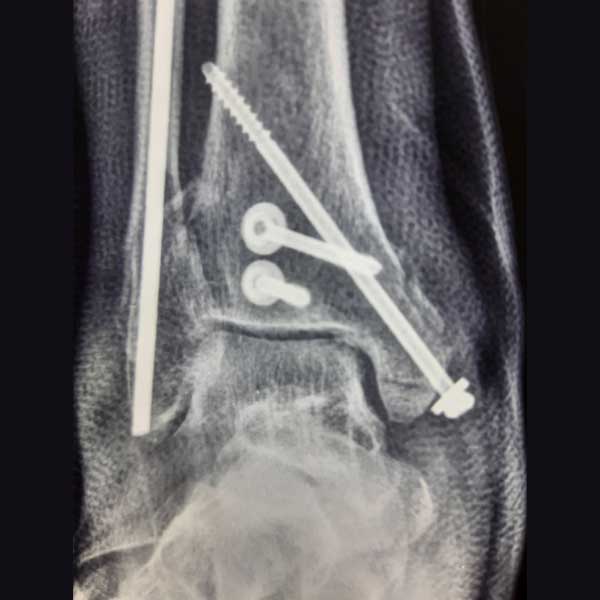

Case:19 Percutaneous fixation with Implants

A male patient, aged 78 years had been diagnosed to have a closed Pott’s fracture Left Ankle. He was treated operatively with Percutaneous fixation with Implants.

Pre-Operative

Post-Operative